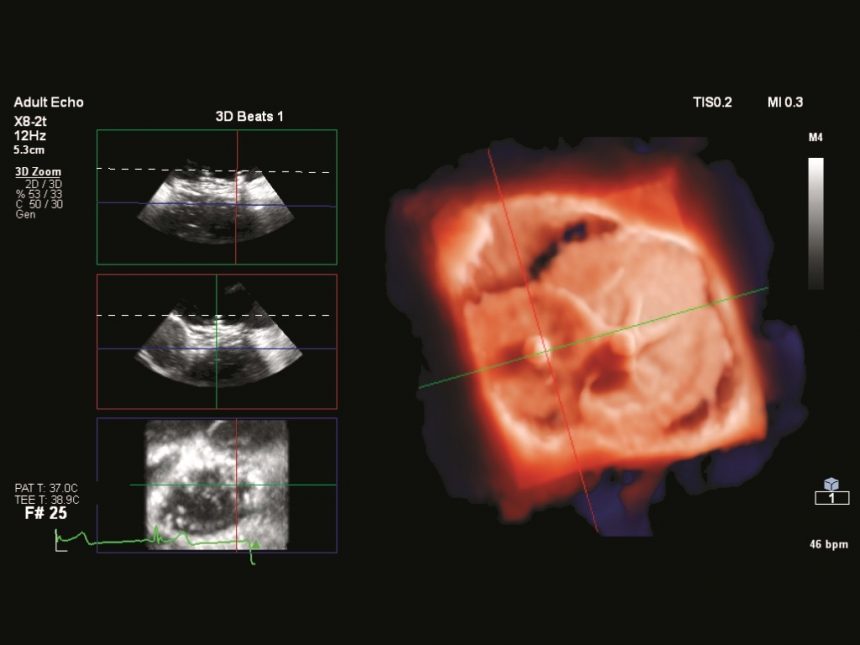

El reconocido cardiólogo argentino Martin Lombardero llega a la ciudad con una muy interesante propuesta para la excelencia del diagnóstico cardiovascular: el mejor equipo de ultrasonido (Eco) cardiovascular, un ecocardiógrafo PHILIPS EPIQ CVx, que incluye un software de Inteligencia Artificial y 3D Cardíaco (Autostrain y Heart Model), Eco-Transesofágico 3D con Transiluminación y 3D Real Time, Cardiac TrueVue, 3D Vascular (inédito en la región), Eco Estrés y múltiples funciones más.